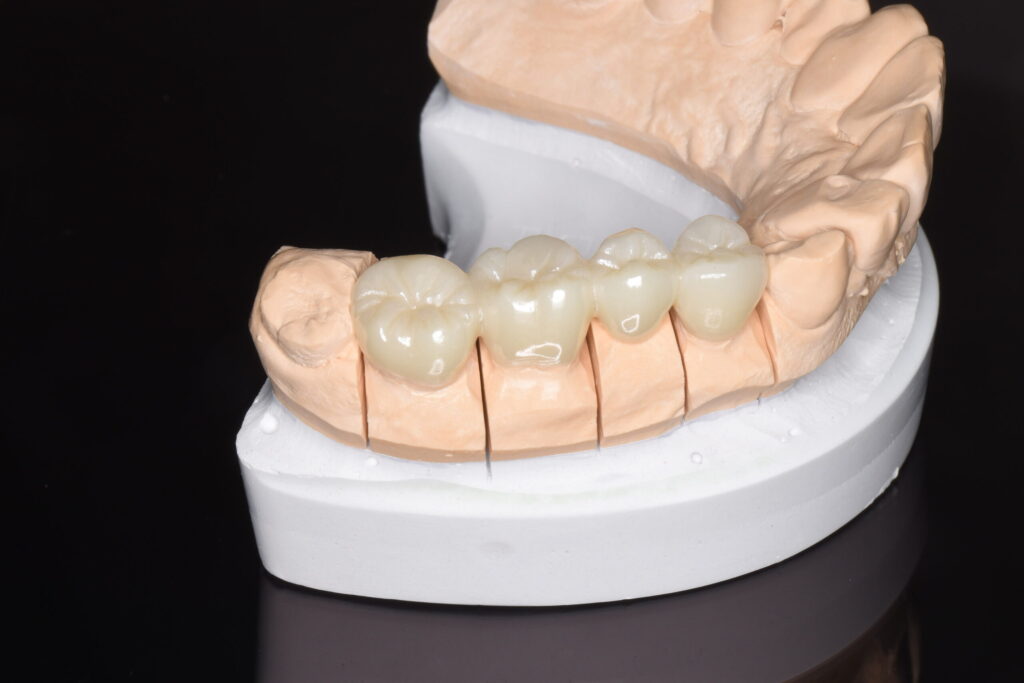

| 銀歯を除去し、ジルコニアブリッジにて補綴処置を行なった。 |

銀歯のブリッジをセラミック(特に強度の高いジルコニア等)へ変える最大のメリットは、「土台となる歯の寿命を延ばせること」にあります。

ブリッジは欠損部分の両隣の歯を支えにするため、土台の歯には常に大きな負担がかかります。銀歯の場合、経年劣化による変形やセメントの流出によって、土台との間に隙間が生じやすく、そこから二次虫歯が進行して土台ごと失うリスクがありました。対してセラミックは変質せず、歯と強固に接着するため、細菌の侵入を許さず土台の歯をしっかり守り抜きます。

また、清掃性の向上も大きな利点です。ブリッジ特有の「汚れが溜まりやすい連結部分」も、表面が滑らかなセラミックならプラークが付着しにくく、日々のケアで清潔を保ちやすくなります。これにより、ブリッジ周辺の歯周病リスクを大幅に軽減できます。